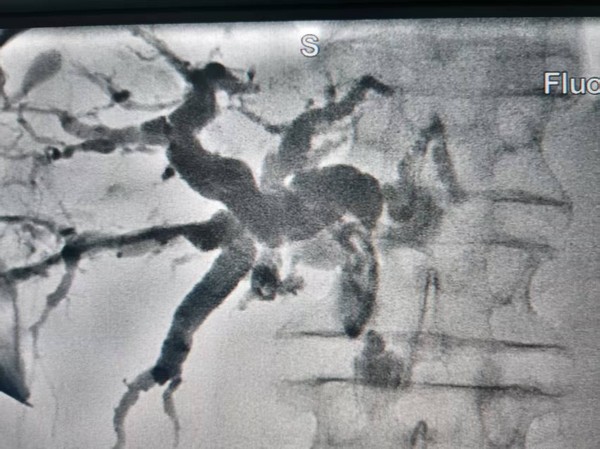

常规开展肺穿刺、肝穿刺、骨穿等检查项目,同步提供免疫治疗、靶向治疗、化疗、内分泌治疗、介入治疗及中西医结合治疗,形成多元化综合治疗体系。在肺癌、胃癌、胰腺癌、卵巢癌、乳腺癌、淋巴瘤、肝癌、膀胱癌、多发性骨髓瘤、再生障碍性贫血、慢性粒细胞白血病等疾病治疗中,积累了独特临床经验。